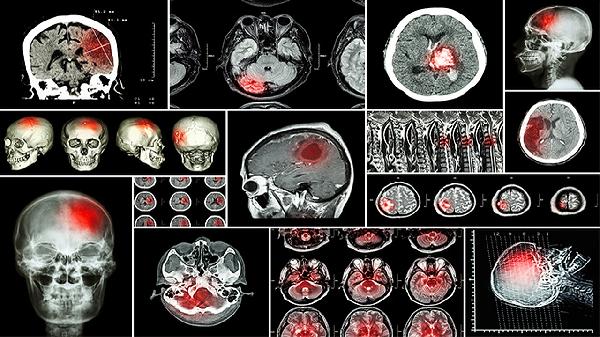

脑部供血不足患者应保持规律作息,避免熬夜和过度劳累。饮食宜清淡,多摄入新鲜蔬菜水果,限制高脂肪、高盐食物。适度进行有氧运动如散步、太极拳等,避免剧烈运动。戒烟限酒,定期监测血压、血脂等指标。若症状持续或加重,应及时就医完善头颅CT、血管造影等检查,明确病因后针对性治疗。